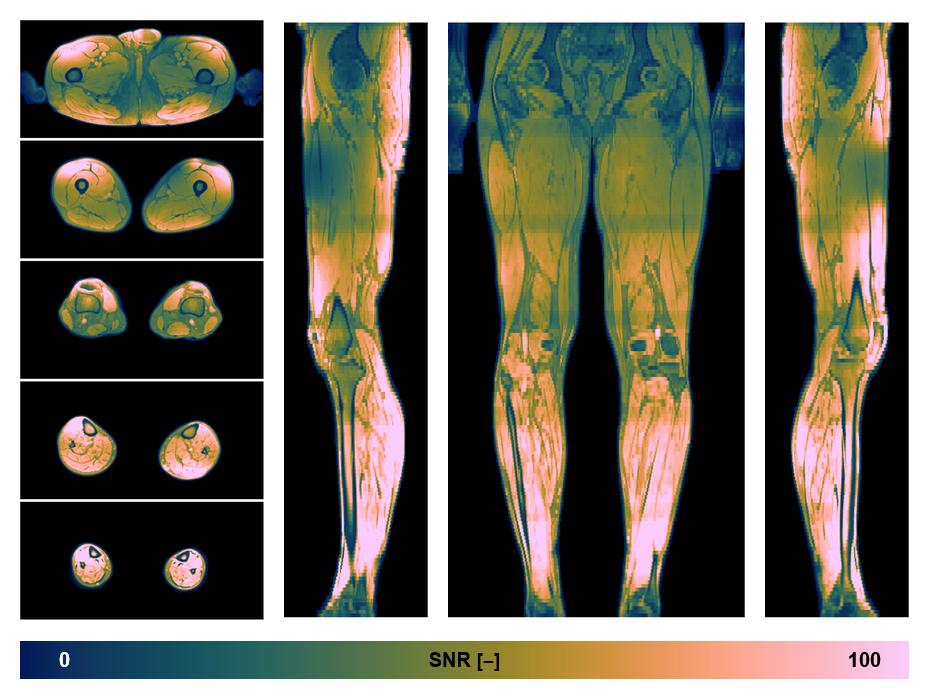

• SNR distribution

The SNR distribution of the dixon data.